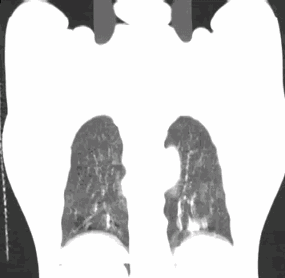

A4D软件测量

呼气末

吸气末

使用A4D软件测量,肿瘤随呼吸周期的运动幅度近24mm。